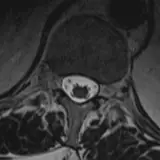

Over 2,100 interactive radiology cases, curated by radiologists for your level of training. Scroll, window, and view cases full screen — just like on PACS. Click linked findings in each writeup to jump straight to them on the image. Cases include sample reports, a focused discussion section, original illustrations, and videos.

Des cas entièrement interactifs avec les outils attendus d'un PACS — défilement, fenêtrage, zoom, déplacement, mesures, ROI et mode plein écran.

Des annotations détaillées mettent en évidence les résultats clés directement sur les cas. Cliquez sur les résultats liés dans les descriptions de cas pour accéder à leur emplacement exact sur l'examen.